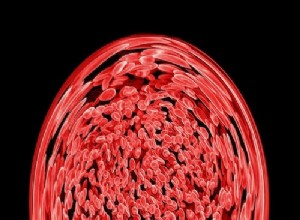

Un appareil innovant qui "écoute" les globules rouges pour détecter les maladies